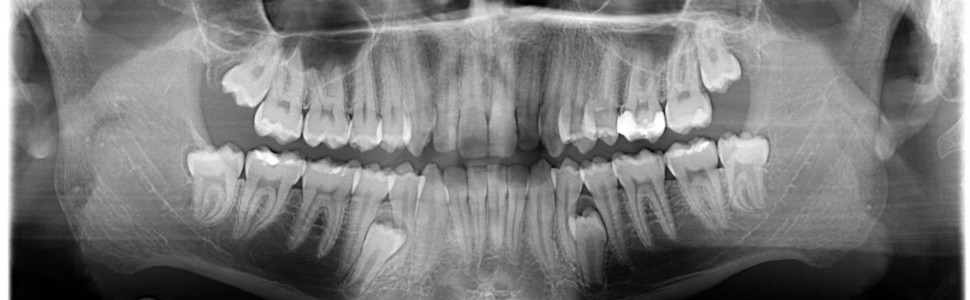

Zaburzenia liczbowe zębów dotyczą coraz większej grupy pacjentów. Występują one w uzębieniu zarówno mlecznym, jak i stałym. Najczęściej lokalizują się w odcinku przednim, ale mogą powstawać w każdym regionie łuków zębowych. Etiologia tego zaburzenia nie została do końca poznana, choć istnieje wiele hipotez dotyczących przyczyn nieprawidłowości.

Teeth numerical disorders are more common nowadays. They could be visible in both deciduous and permanent teeth. Most common place for them is frontal part, but they can appear in any part of dental arch. Reason for that disorder is not completely known, but there are many hypothesis about it.